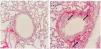

In order to ratify the lung impairment, we also evaluated the histological pattern of adenine-induced CKD mice, and our findings on a qualitative increase in collagen content in lungs of CKD group, as shown in Fig. 4.

Lung histologyThe left lung of each animal was separated in order to prepare slides stained with Picro-Sirius Red, for qualitative assessment of collagen fibers content.